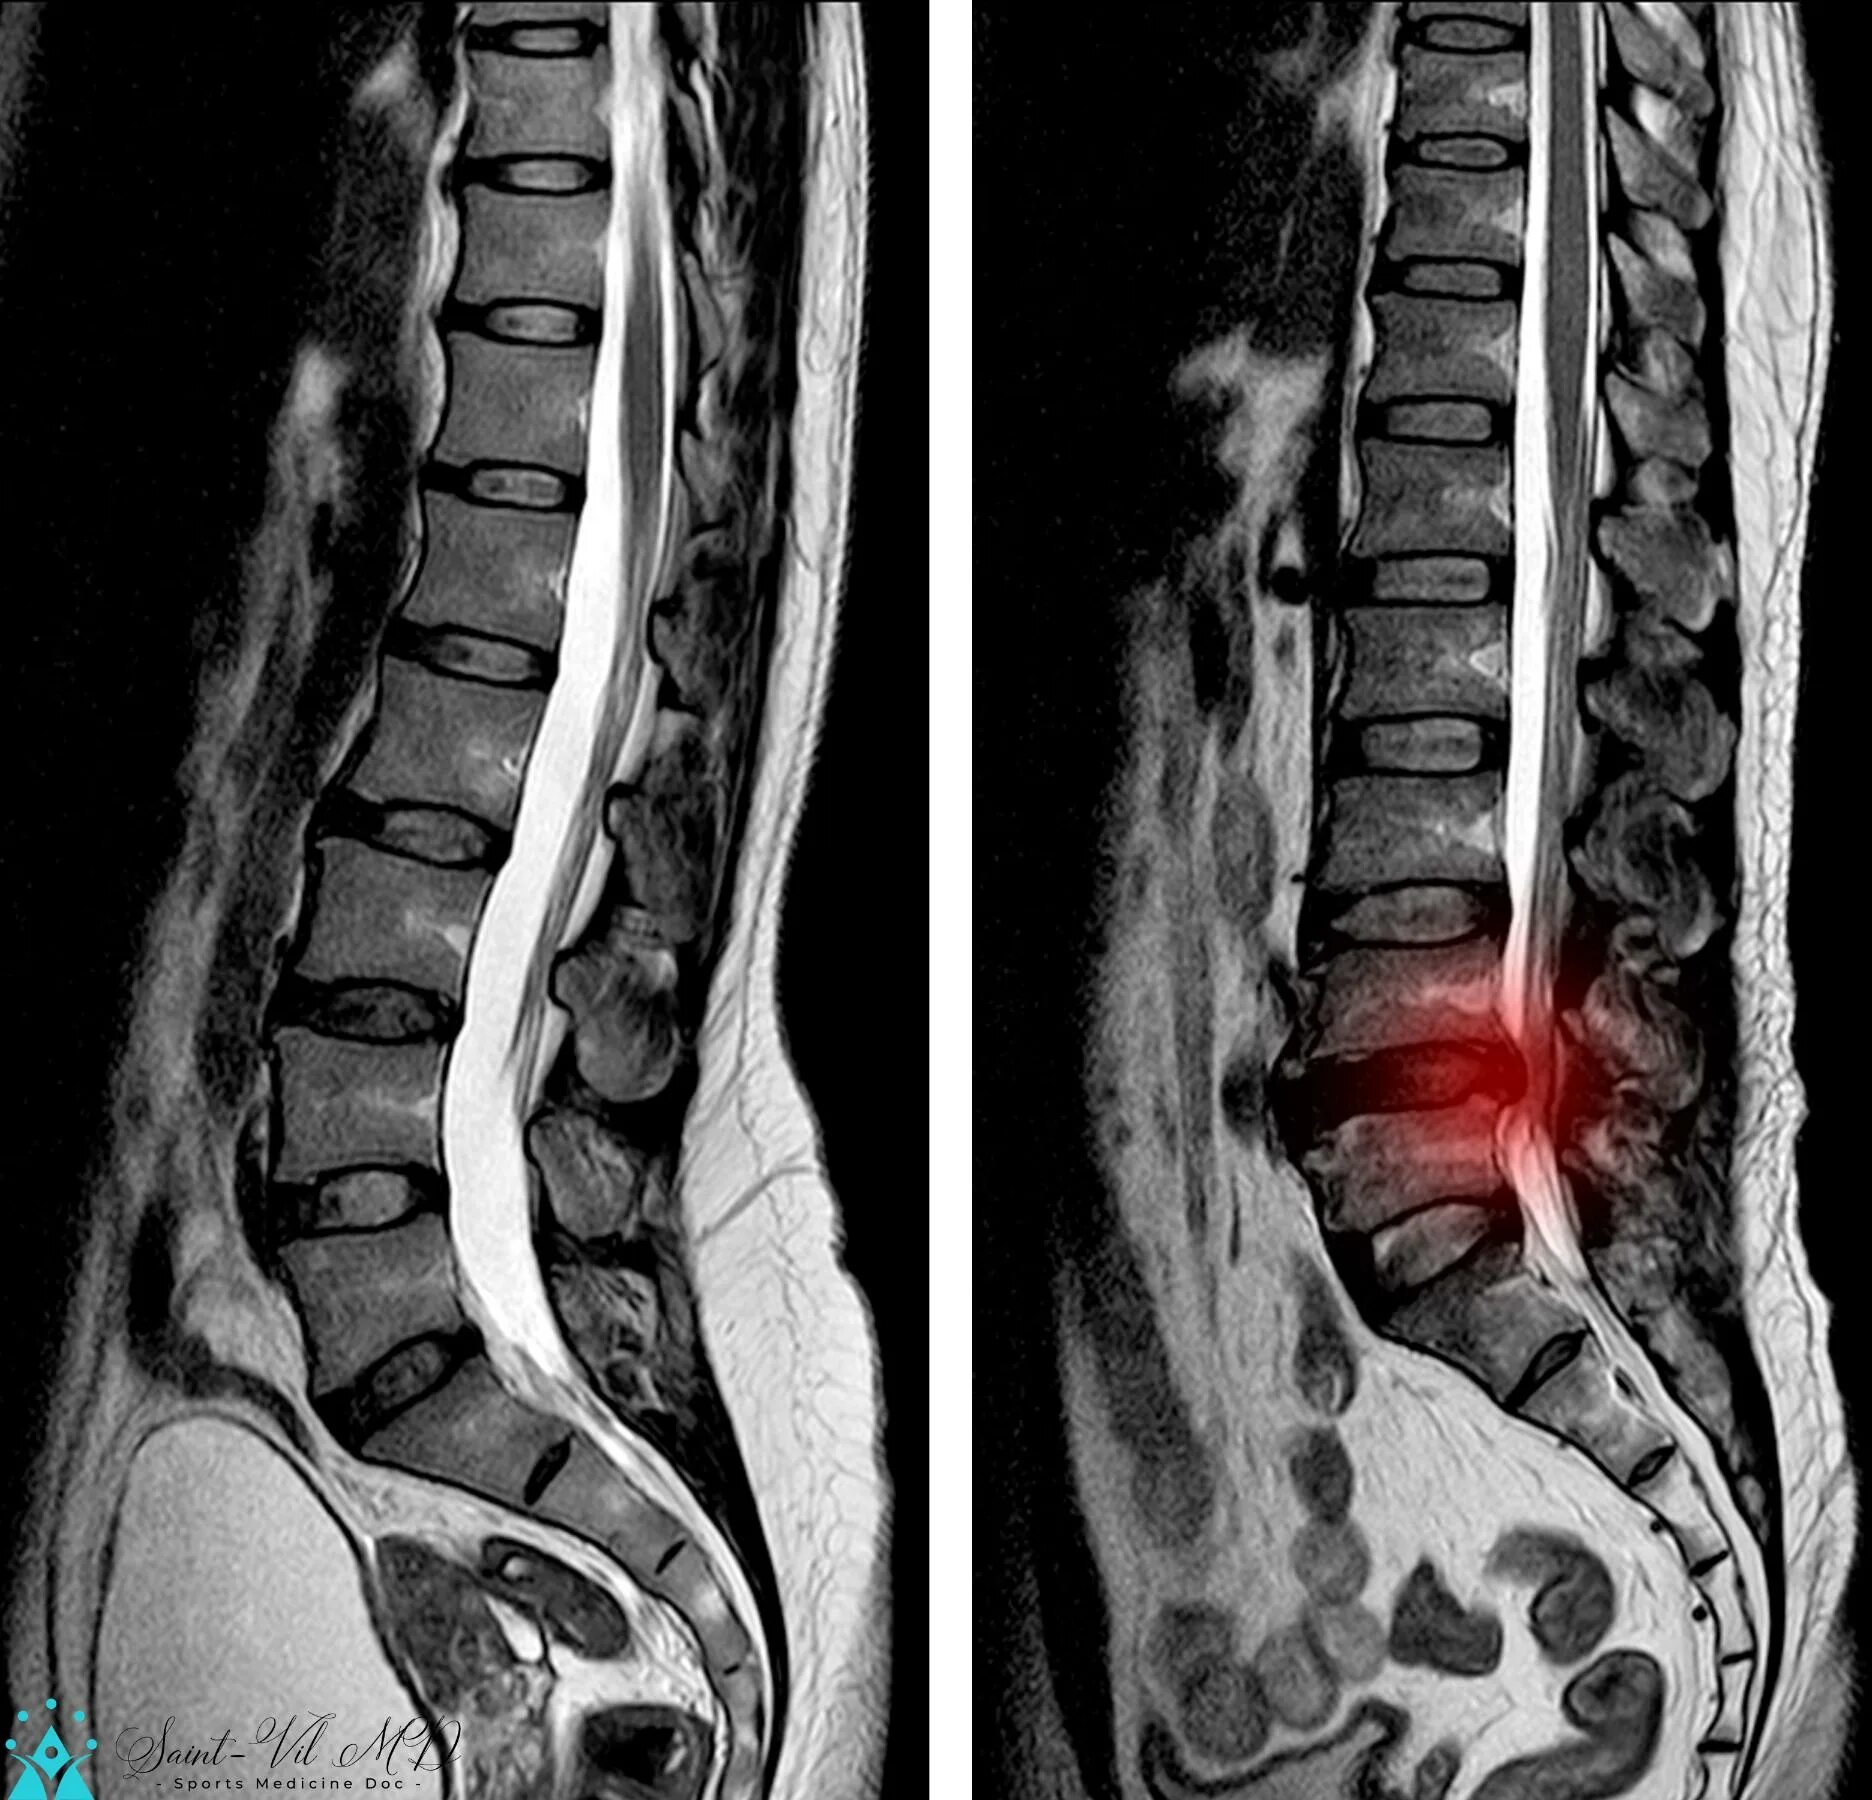

Сегмент l1 l5